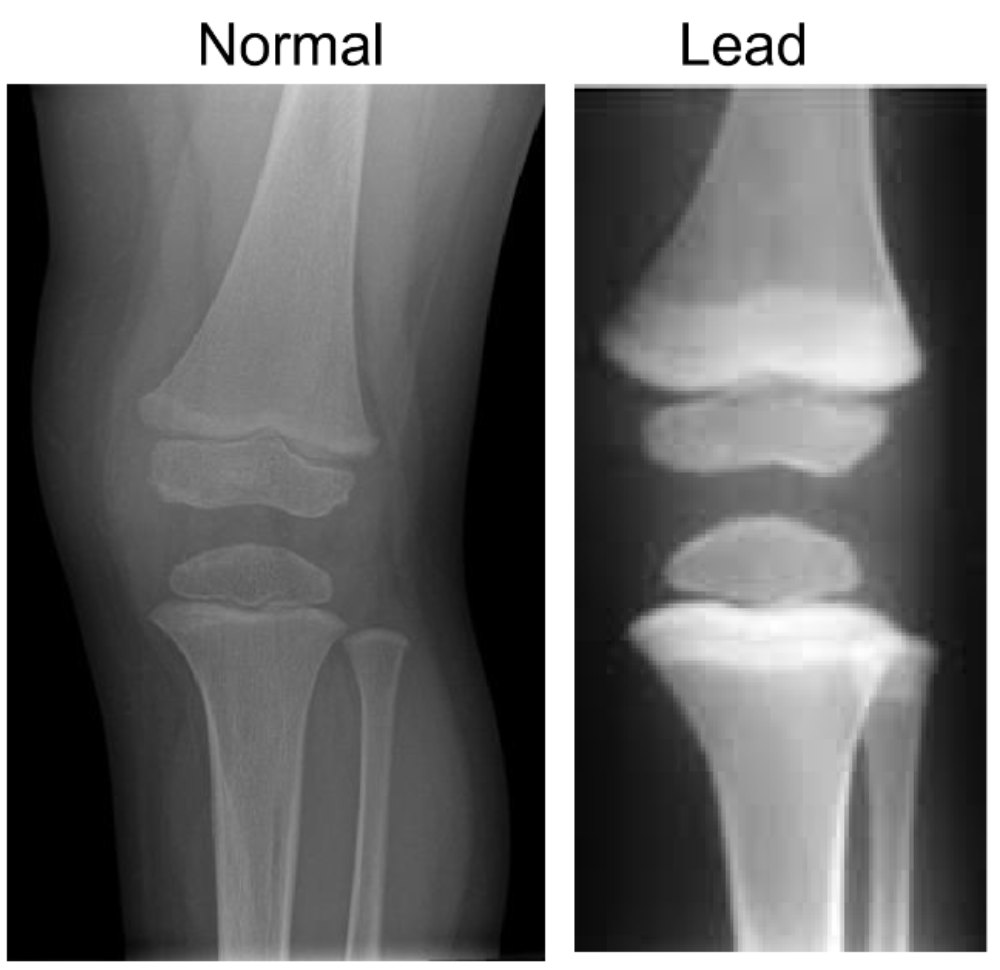

what are the effects on bone?

A

-lead substitutes for calcium in bones

-impacts on osteoblasts-> delayed fracture repair